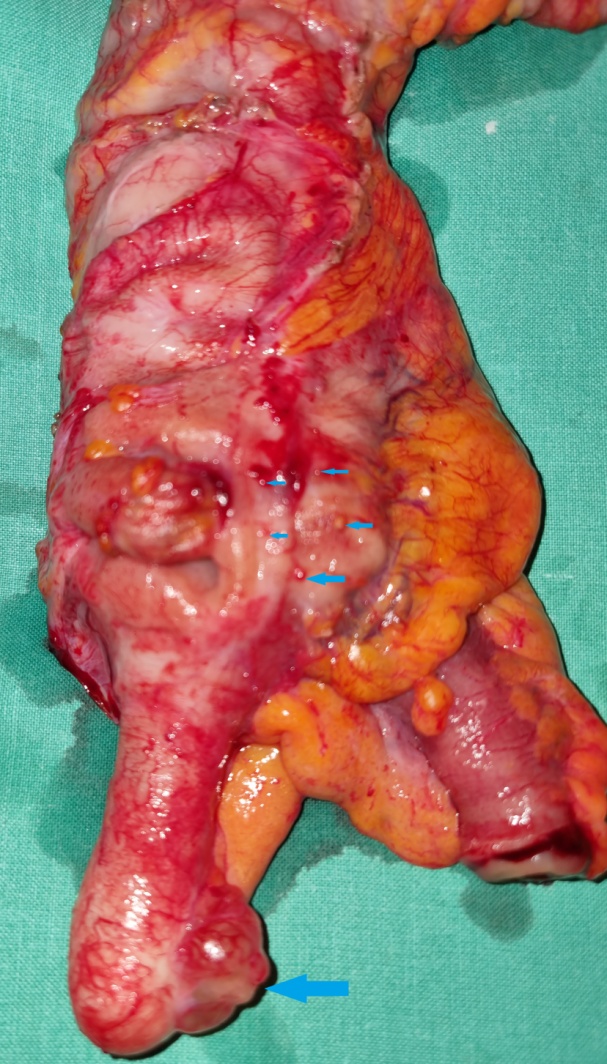

Εκτομαθέν τμήμα τελικής κολοστομίας. Μπλε βέλη — Θέσεις εκκολπώσεων (Ευγενική παραχώρηση Dr. V. Penopoulos)

Μη φλεγμαίνουσες εκκολπώσεις στο κολικό τμήμα αμέσως κάτω από την εξωτερικευμένη τελική κολοστομία (Ευγενική παραχώρηση Dr. V. Penopoulos)